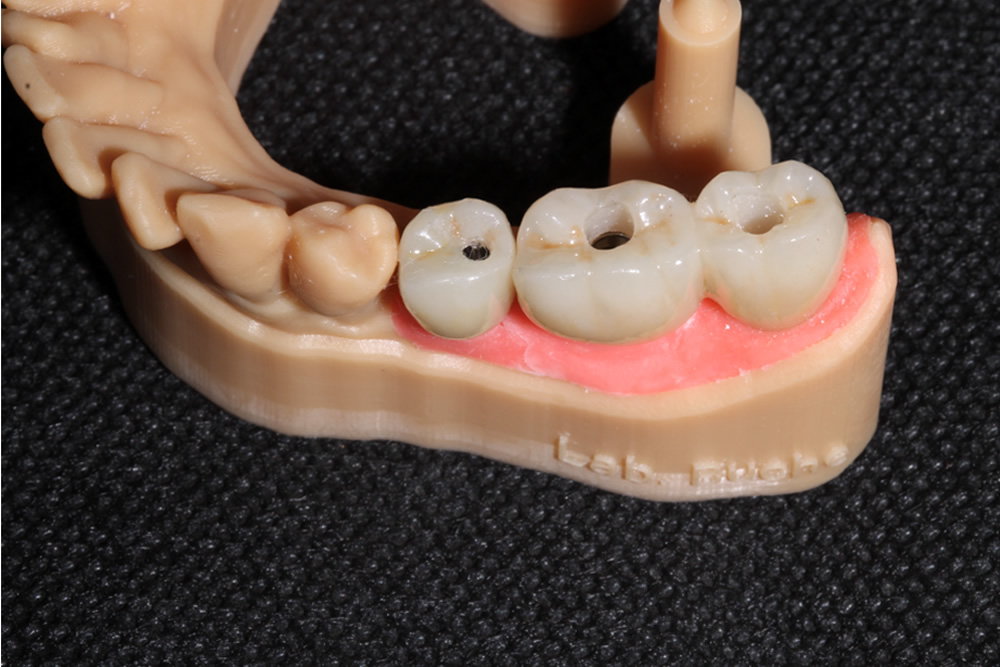

Próteses Fixa sobre implante

É utilizada para substituir ,através de implantes intra-ósseo, dentes já condenados que foram, ou ainda precisam ser extraídos. É a melhor opção capaz de restabelecer função mastigatória, conforto e estética, seja em casos de reabilitação de um único dente ou até de uma arcada dentária inteira (protocolo). As próteses sobre implante podem ser produzidas com diversos materiais, e esta escolha se torna fundamental para um resultado estético favorável.